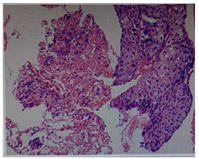

2020年7月15日气管镜:左支气管各管腔通畅,未见新生物及狭窄;右上叶支气管尖段开口见新生物生长,堵塞管腔(图1),活检易出血;右中、下叶管腔通畅,未见新生物及狭窄。刷检涂片查见癌细胞,活检病理提示鳞状上皮呈高级别上皮内瘤变(图2),局部考虑癌变。